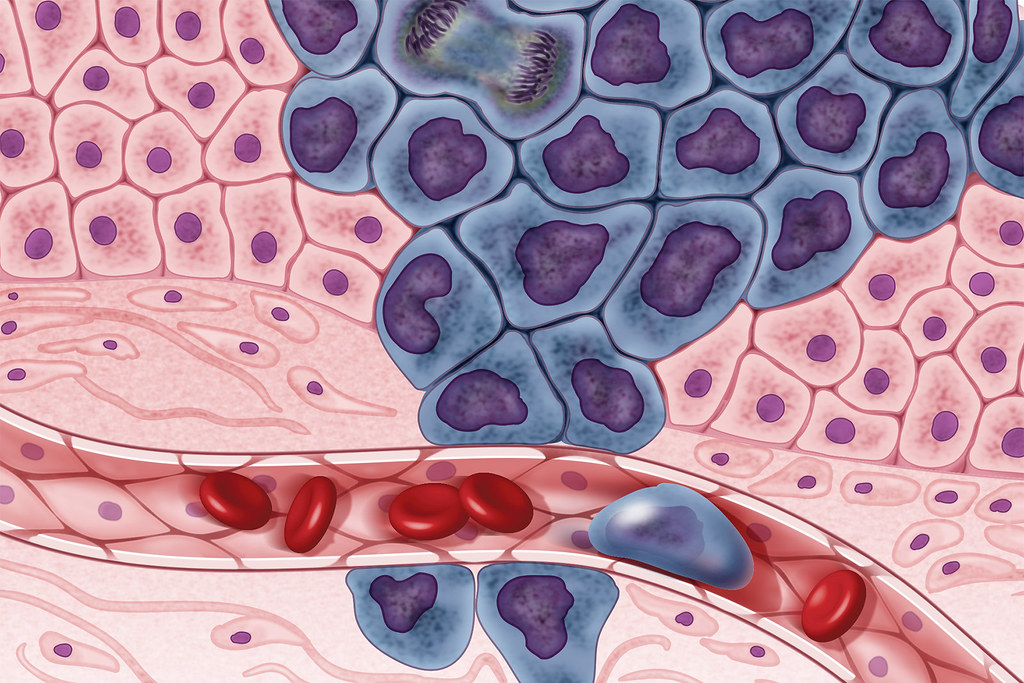

Známa aj ako adjuvantná terapia, je liečebná stratégia, ktorá sa aplikuje po chirurgickom odstránení nádorového tkaniva. Cieľom tejto liečby je eliminovať mikroskopické rakovinové bunky, ktoré mohli zostať v tele po operácii. Tieto bunky sú často príliš malé na to, aby boli viditeľné pomocou súčasných diagnostických metód, no môžu byť zdrojom recidívy ochorenia, ak sa neodstránia.

Monica Avila, onkologička z Moffitt Cancer Center, uvádza, že hoci chemoterapia je často považovaná za agresívnu liečbu, jej preventívna forma je určená len pre pacientov, ktorí už majú diagnostikovanú rakovinu. Chemoterapia sa nikdy nepoužíva na prevenciu rakoviny u zdravých jedincov. Adjuvantná chemoterapia sa zameriava na zvyškové rakovinové bunky, aby sa znížila šanca na opätovný výskyt choroby.

Preventívna chemoterapia je dôležitá preto, že aj po úspešnom chirurgickom odstránení nádorového tkaniva existuje riziko, že v tele zostanú mikroskopické zvyšky rakovinových buniek. Tieto bunky môžu časom prerásť do nových nádorov, ktoré by mohli ohroziť život pacienta. Preto lekári často odporúčajú adjuvantnú chemoterapiu ako spôsob, ako minimalizovať toto riziko.